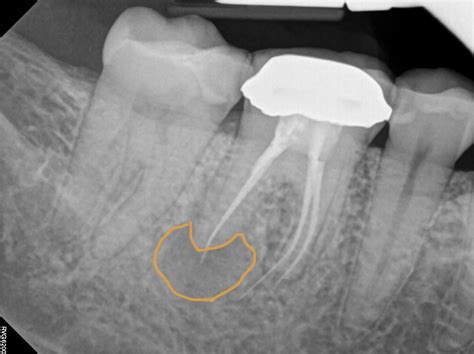

Professional dental intervention is the only way to treat a root abscess effectively. A dentist will typically perform an X-ray to confirm the diagnosis and determine the extent of the infection. Treatment options generally include:

• Root canal treatment: Removing the infected pulp from the tooth and sealing the root canal to prevent further infection.

A root abscess is a localized collection of pus caused by a bacterial infection at the root of a tooth. This infection typically occurs when bacteria enter the tooth through deep cavities, fractures, or failed dental work, reaching the pulp—the inner part of the tooth that contains blood vessels and nerves. As the body attempts to fight this infection, it sends white blood cells to the area, resulting in the formation of pus. If this pus cannot drain, it forms an abscess, leading to intense pain and potentially serious complications.